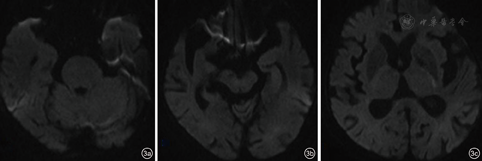

患者,女性,91岁,因"突发反应迟钝伴左侧上下肢无力1 d"入院。患者16 h前出现神智模糊,反应迟钝,活动减少,不愿进食,无呕吐,无二便失禁,无肢体抽搐;2 h前意识障碍加重,伴有头痛、呕吐,遂于安徽医科大学附属合肥医院急诊科就诊,急诊头颅CT提示左侧小脑出血(图1),收入神经内科。患者既往高血压病史多年,不规则服用降压药物,平时监测较少。查体:体温36.8 ℃,血压230/134 mmHg(1 mmHg=0.133 kPa),双肺呼吸音粗,未闻及干湿性啰音,心率100次/min,律齐,偶闻及期前收缩,未闻及杂音。神经系统检查:嗜睡状,问之无应答,额纹对称,双侧瞳孔直径2.5 mm,对光反射存在,双眼右向凝视,左侧上下肢肌张力低,肌力Ⅱ级,右侧上下肢肌力V-级,右侧上下肢肌张力正常,双侧巴氏征未引出。实验室检查:红细胞计数为3.99×1012/L,中性粒细胞计数为15.36×109/L,中性粒细胞百分数83.21%,白细胞计数为18.48×109/L,尿素氮25.50 mmol/L,肌酐382.0 mmol/L,血钾6.15 mmol/L。心电图提示窦性心动过速。头颅CT提示左侧小脑半球出血,双侧侧脑室旁、丘脑、脑桥大片状低密度灶。入院后即刻予以吸氧、心电监护、促醒、脑保护、抑酸护胃、补液支持、脱水降颅压、调节电解质紊乱等治疗,并静脉滴注硝酸甘油以0.25 mg/h调节血压。入院后约14 h患者出现高热达39.9 ℃、呼吸道分泌物明显,意识障碍进一步加重呈中-深度昏迷,考虑肺炎,予以抗炎、化痰、补液、促醒等处理,持续静脉使用硝酸甘油加量至1 mg/h,血压仍持续达(180~200)/(110~120)mmHg,降压治疗效果差,血尿素氮、肌酐进一步恶化。肺部CT提示慢性支气管炎、肺气肿、右肺炎;头颅MR提示双侧侧脑室旁、丘脑、双侧桥脑、中脑广泛T1WI低、等信号,T2WI及FLAIR像呈高信号,弥散加权成像呈低、等信号,表观扩散系数图无信号(图2、图3)。患者于入院后46 h神志转清,血压(120~130)/(80~90)mmHg,左侧肢体肌力恢复至Ⅳ级,要求下床小便,停用硝酸甘油,加用口服非洛地平缓释片5 mg,2次/d,联合厄贝沙坦氢氯噻嗪片1片,1次/d调节血压,余治疗继续予以原方案。半个月后复查头颅MR除小脑出血病灶存留,其余异常信号完全消失(图4)。入院25 d后患者病情稳定,血压120/70 mmHg,可自主进食、正常交流及下床自行活动,予以出院。随访1个月病情无反复。

RPLS病灶主要累及大脑半球后部,如顶叶、枕叶、额颞叶、小脑、基底节及脑干等。中央变异型RPLS可伴有丘脑或脑室旁白质受累[6,9]。本例患者是双侧对称的脑干、丘脑、脑室旁受累,该类型常与高血压密切相关,及时诊断及治疗后大多临床转归较好[1,2,10]。